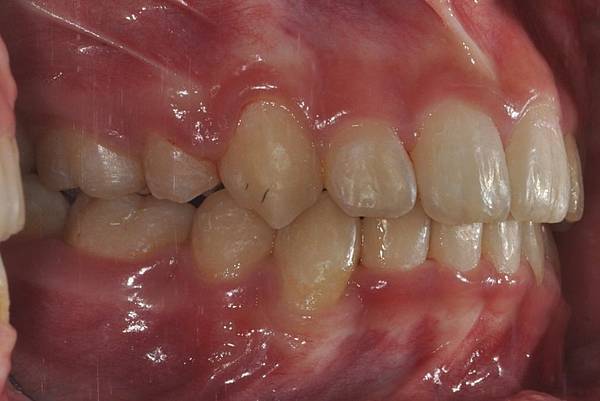

拔牙改善高位虎牙

虎牙妹的女神蛻變之旅~

此案例因為空間不足排列牙齒,

考量到不拔牙將使得牙齒前凸破壞患者原本和諧的側臉。

故上下左右各拔一小臼齒。

治療前/治療後

-以上案例由林昇進醫師提供